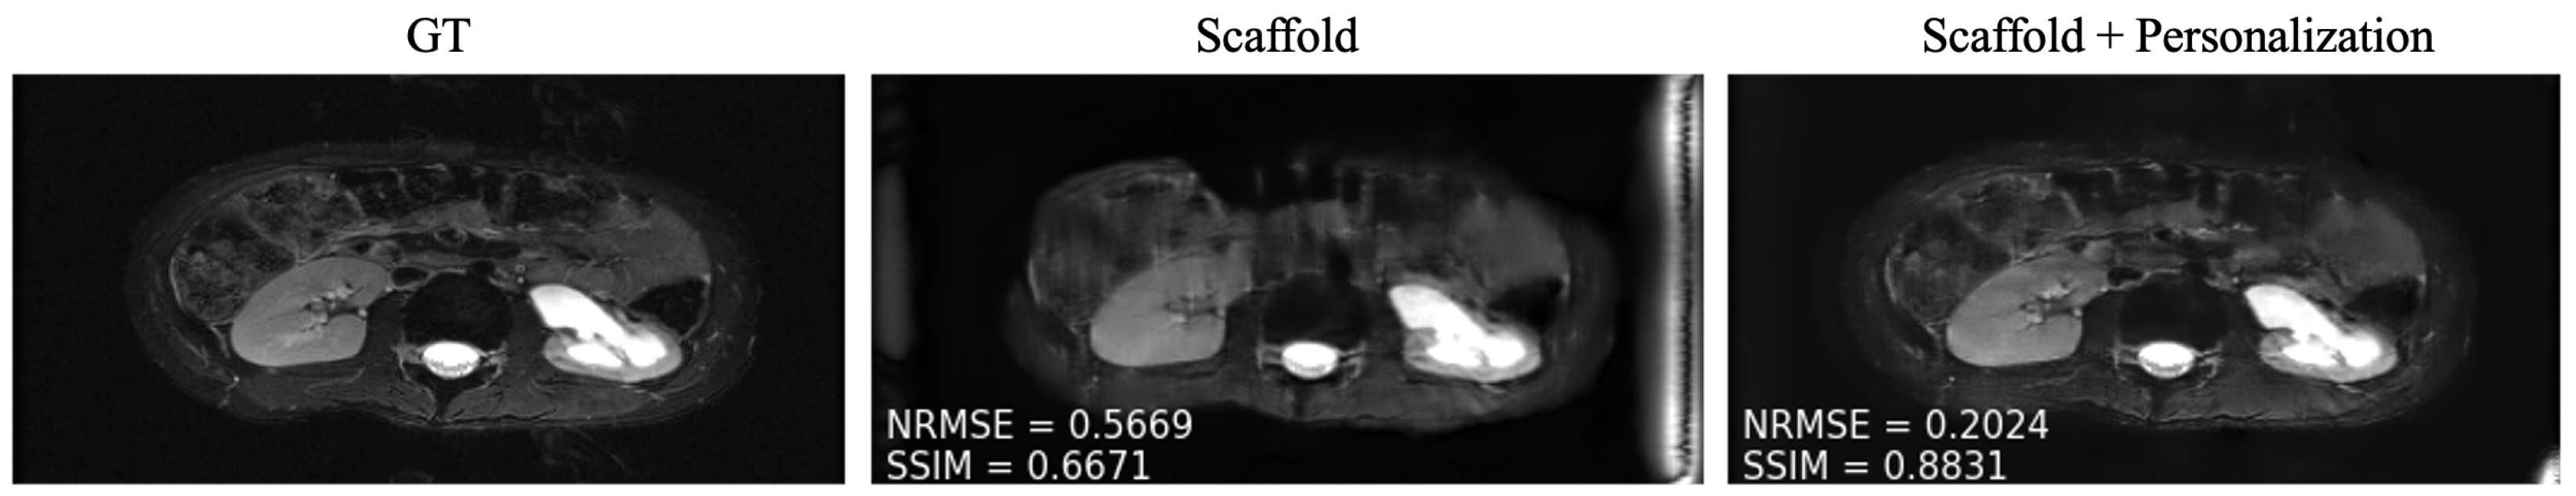

4.3. Personalization and Impact of Communication Budget

As mentioned in Section 3.4, after training, we personalized the model at each new site through fine tuning. We tuned two client-specific hyper-parameters ( r fine and N fine ) at one seen site (site 2) and two unseen sites (Stanford and NYU axial knee) using a five-fold cross-validation scheme on the available 50 local slices. The resulting hyper-parameters are displayed in Table 4. We picked site 2 (fastMRI, fat suppressed knee, 3T) from the sites present during training because it comes from the anatomy less represented among all clients, leaving room for more personalization gains similar to the unseen sites during training. Exemplar reconstructions are shown for one out-of-distribution client (Stanford abdomen) at 240 communication rounds and one in-distribution client (site 2) at four communication rounds in Figure 5 and Figure 6, respectively. In both cases, there is a substantial drop in performance for Scaffold, which is recovered after fine tuning.

Figure 5. Example reconstructions on a new client (Stanford) using (Center) only the pre-trained Scaffold model, (Right) Scaffold + personalization.

Bioengineering 10 00364 g005